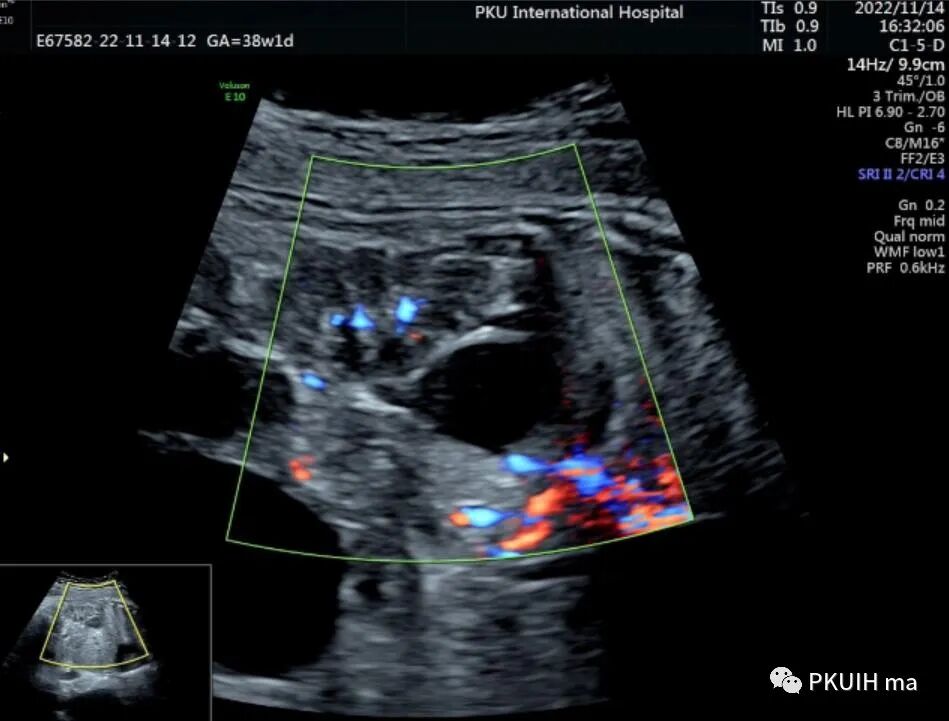

肾上腺出血的超声表现谱取决于所见血肿的不同阶段,新鲜出血呈高回声,随后发展呈弥漫回声的固体血块,不断地收缩。最后,当液化发生时,图像显示混合回声,并最终呈无回声。肾上腺出血可以在随访中发现肿块消失。

正常情况下,产前超声能够区分腹腔肿块和肾上腺区肿块。肾上腺区肿块的主要鉴别诊断是先天性成神经细胞瘤、隔离肺、肾上腺出血、中胚层性肾瘤和尿道肠道的重复畸形。排除的最重要的病变是成神经细胞瘤。成神经细胞瘤超声图像呈均匀实性回声,部分可呈囊实混合回声,内可见钙化,CDFI肿块内见血流信号,极少部分成神经细胞瘤可呈囊性回声。肾上腺囊性占位需要定期随访,生后没有标准的治疗方案,如果是单纯囊肿<3cm患儿没有症状只需要定期超声。如果出现内分泌失调,生长迅速等需要手术治疗。

大多数产前诊断的肾上腺肿块是囊性神经母细胞瘤。在出生前诊断出的其他肿瘤包括肾上腺和皮质肾囊肿,间质肾和重复肾。此外,BWS(常与肾上腺肿瘤和肾上腺出血相关)的诊断也必须考虑在内。大多数神经母细胞瘤病例在妊娠晚期才被诊断出来,尽管早期已经进行了扫查。胎儿神经母细胞瘤的超声表现为囊性、均匀回声和高回声,并伴有混合的钙化灶,与胎儿肾上腺出血的鉴别有时相对困难,特别是因为一些血管丰富的神经母细胞瘤伴有瘤内出血。